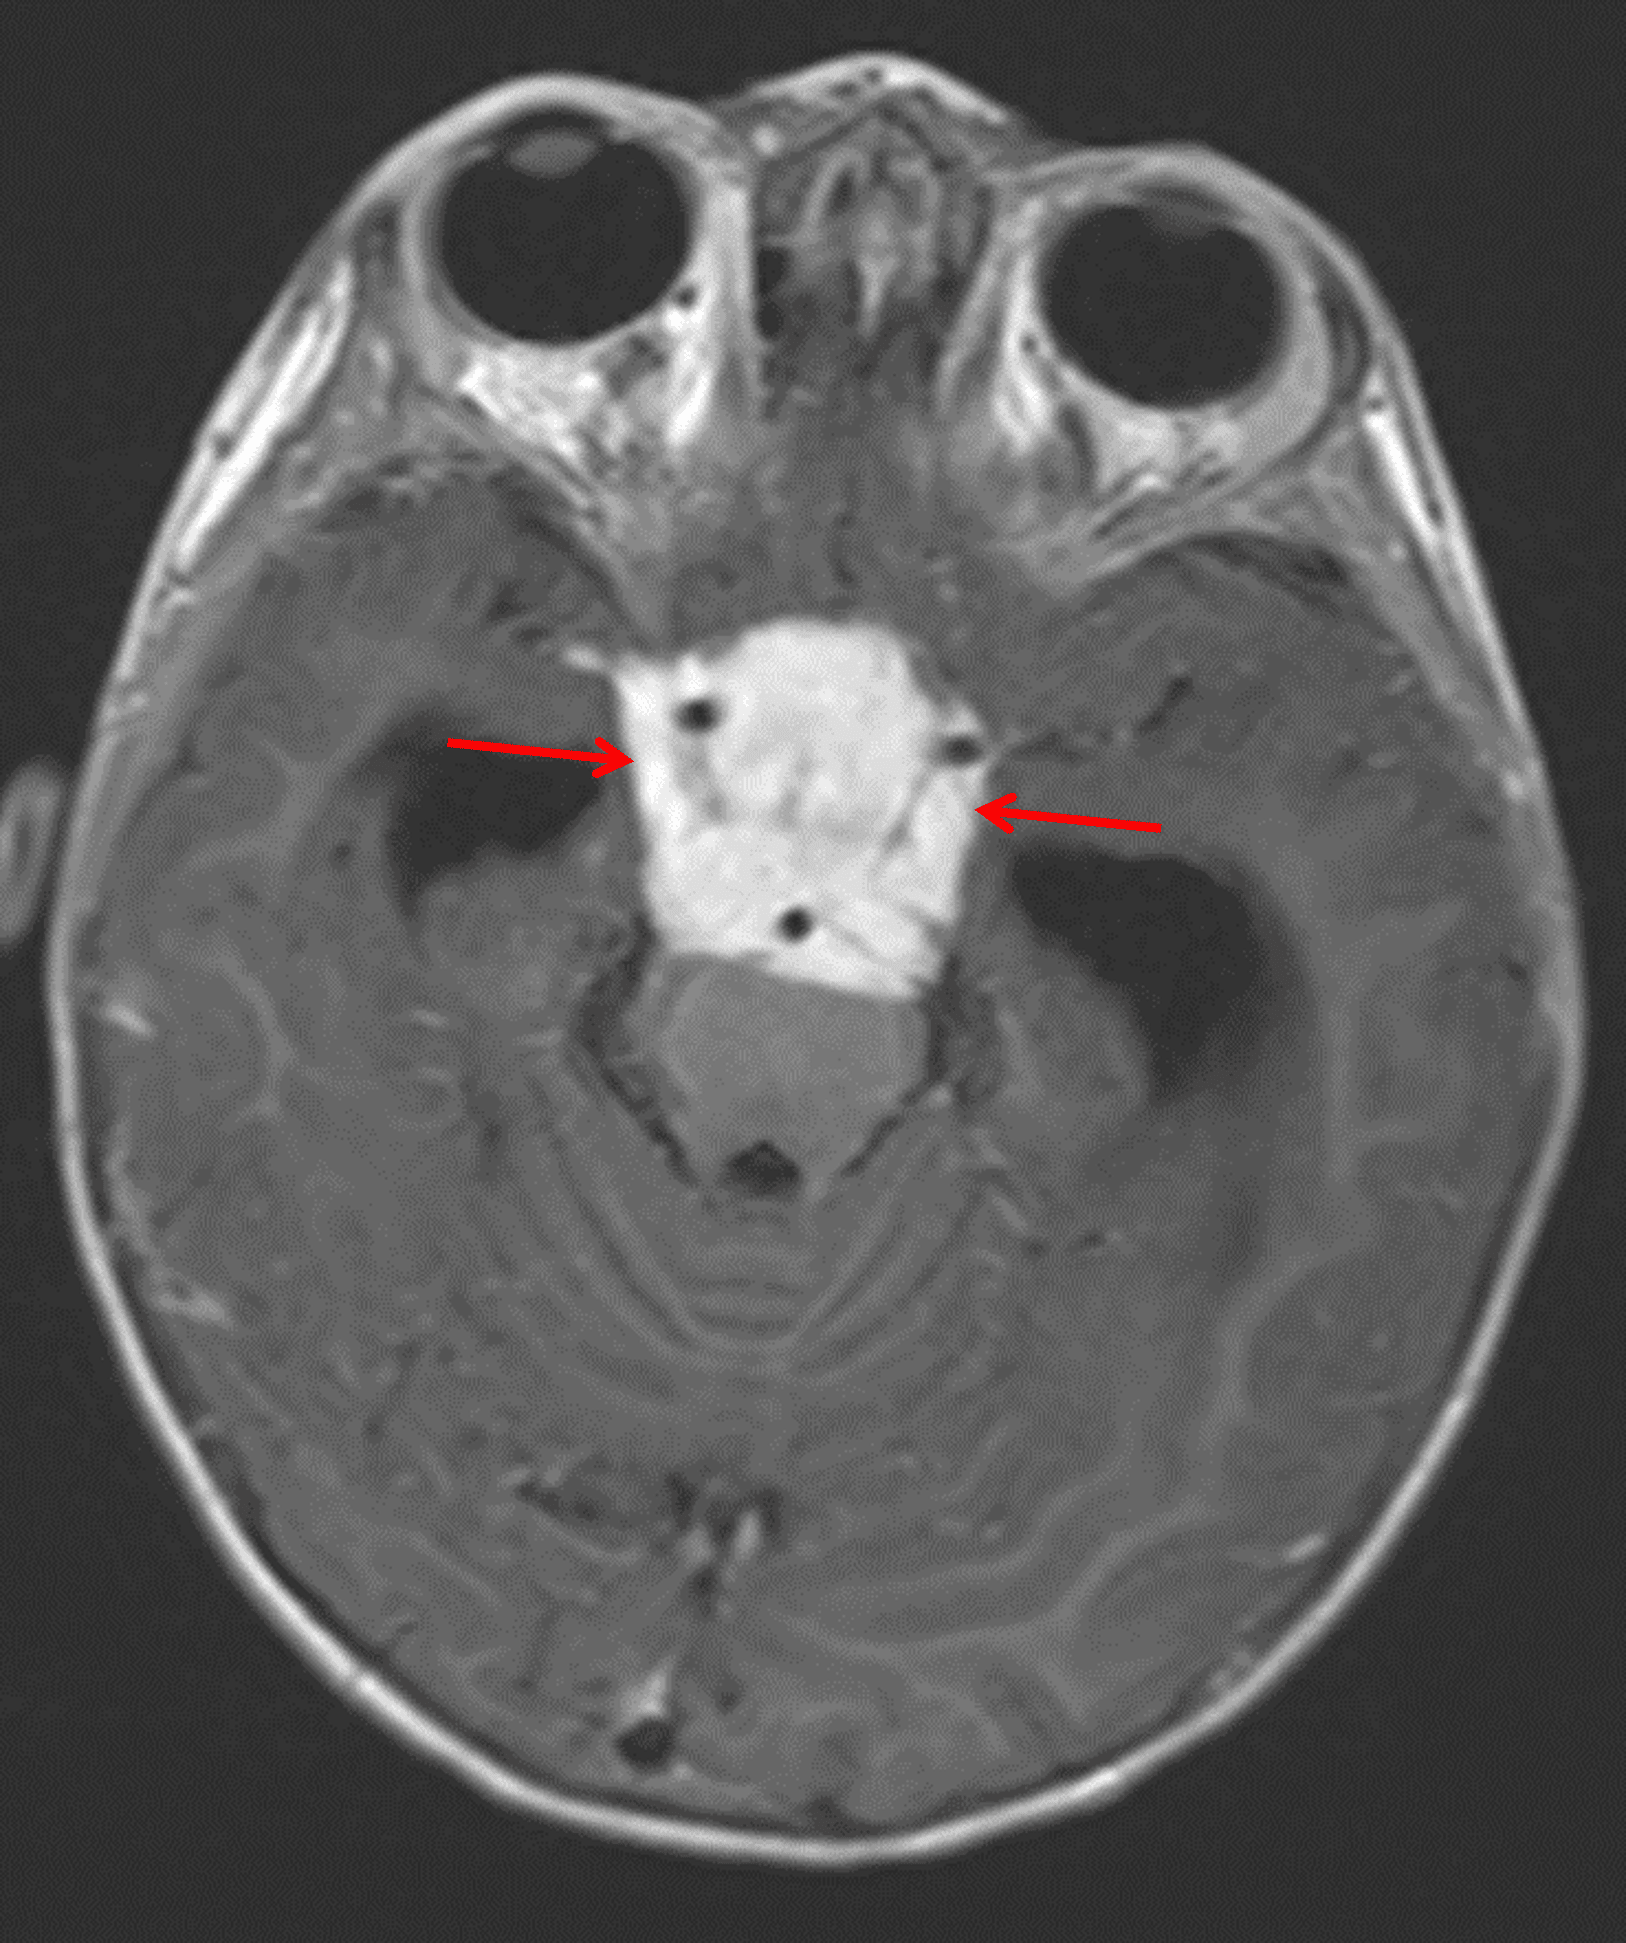

Corresponding avid enhancement (red arrows). The mass encases multiple vascular structures and extends into the prepontine cistern with mass effect on the pons.